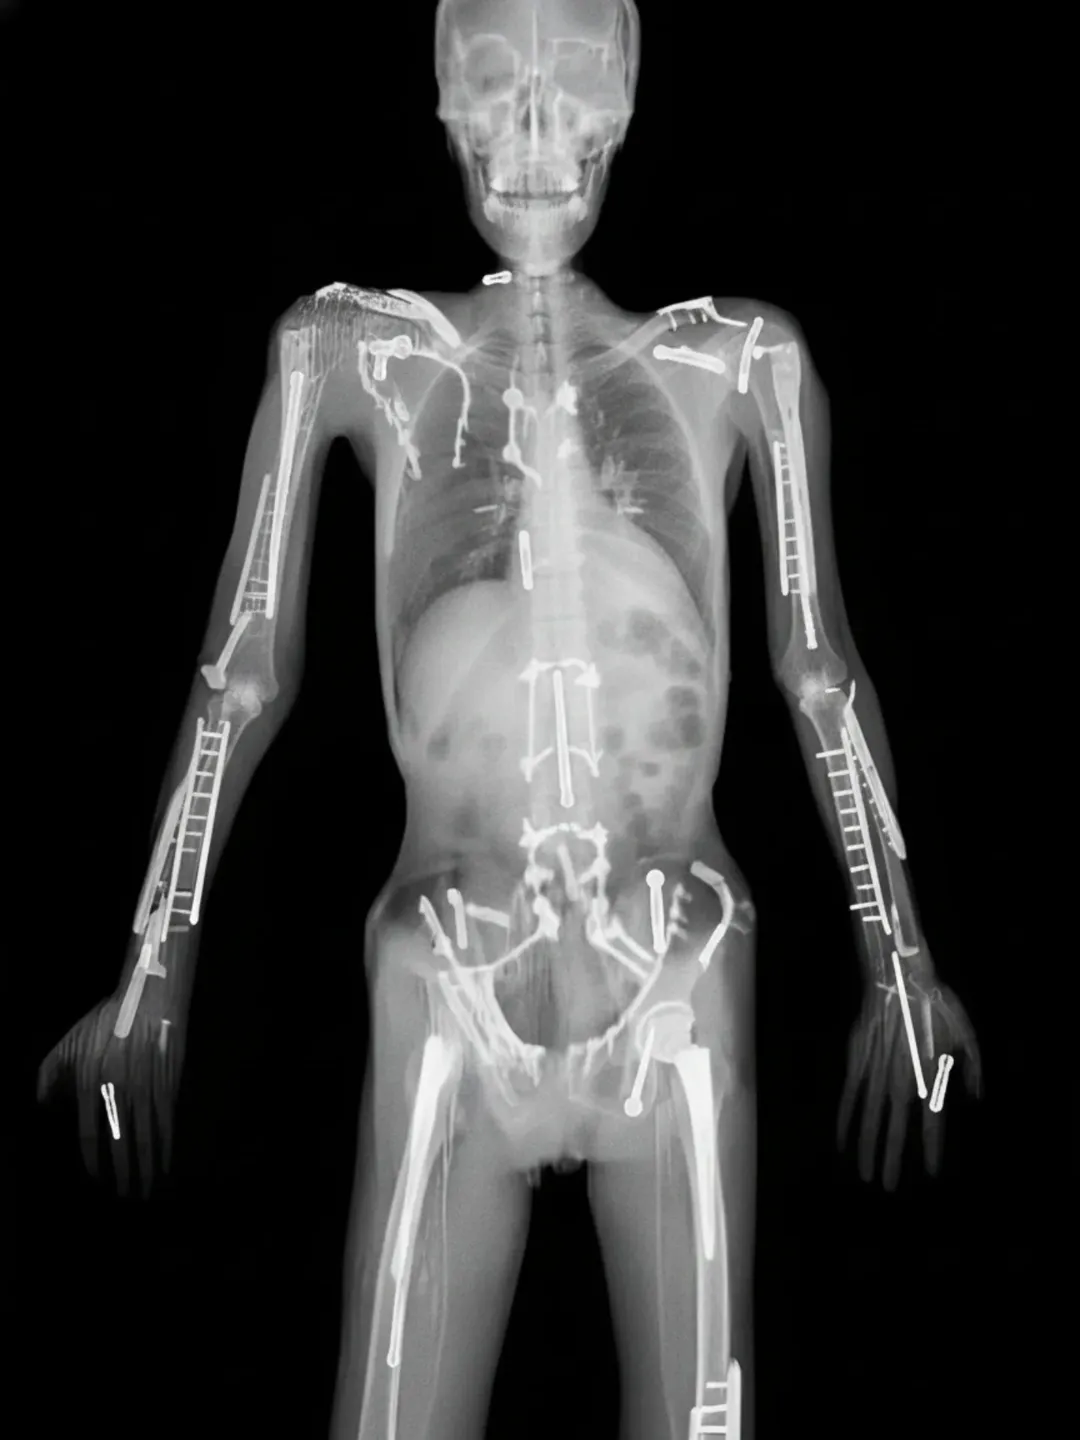

ここまですると改造人間だな

こんなのを何十何百やってる人だからな…

サイボーグじゃん…

骨を全部チタンに変えたらって思いかねないほどボルトと添え木だらけだな…

まあ画像のはどう見てもAIなんだが…

>まあ画像のはどう見てもAIなんだが…

調べたらすぐ出てくるのにAI扱いされるトラビス・パストラーナ…

実際はきっちりと処置してるんだろうがスレ画だけ見ると雑に継ぎ接ぎしてね?ってなる

これじゃ改造人間じゃなくて修復人間だよー